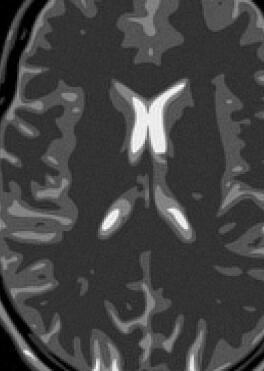

Fig. 14 exhibits the reconstruction results with the spiral trajectory with for . The reconstructed images are displayed alongside profile plots of row . The same is also presented in Figures 13 for .

When sampling on a spiral trajectory, SPURS further demonstrates its superior performance over the other methods. For values high enough, SPURS, NUFFT and rBURS with achieve very good results, but the performance curve for each method levels off for different values of (Figures 9, 10, 11 and 12). Iterative SPURS levels off for values as low as , requiring about iterations to converge to its best result. For these low values, significant artifacts appear in the reconstructed image produced by all methods excluding SPURS as presented in Fig. 13 for and Fig. 14 for . The performance curve of the NUFFT method and of a single iteration of SPURS level off at around . For and higher, a single iteration of SPURS produces marginally better results than those produced by NUFFT, which requires about iterations to converge. Among the other non-iterative methods, both rBURS with and convolutional gridding perform similarly well for , however the results are still inferior to those of a single iteration of SPURS, all of which have similar computational complexity.